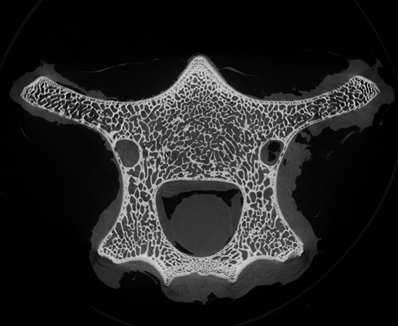

小編很好奇在micro CT掃描中,這些笑臉會是什么樣子?我們選擇了一段羊的脊椎骨放入CT設(shè)備中進行掃描,在得到的幾百張切片圖中,挑選出一張“萌萌的大笑臉”。

Step1. 獲得CT三維體數(shù)據(jù)

骨骼CT切片圖